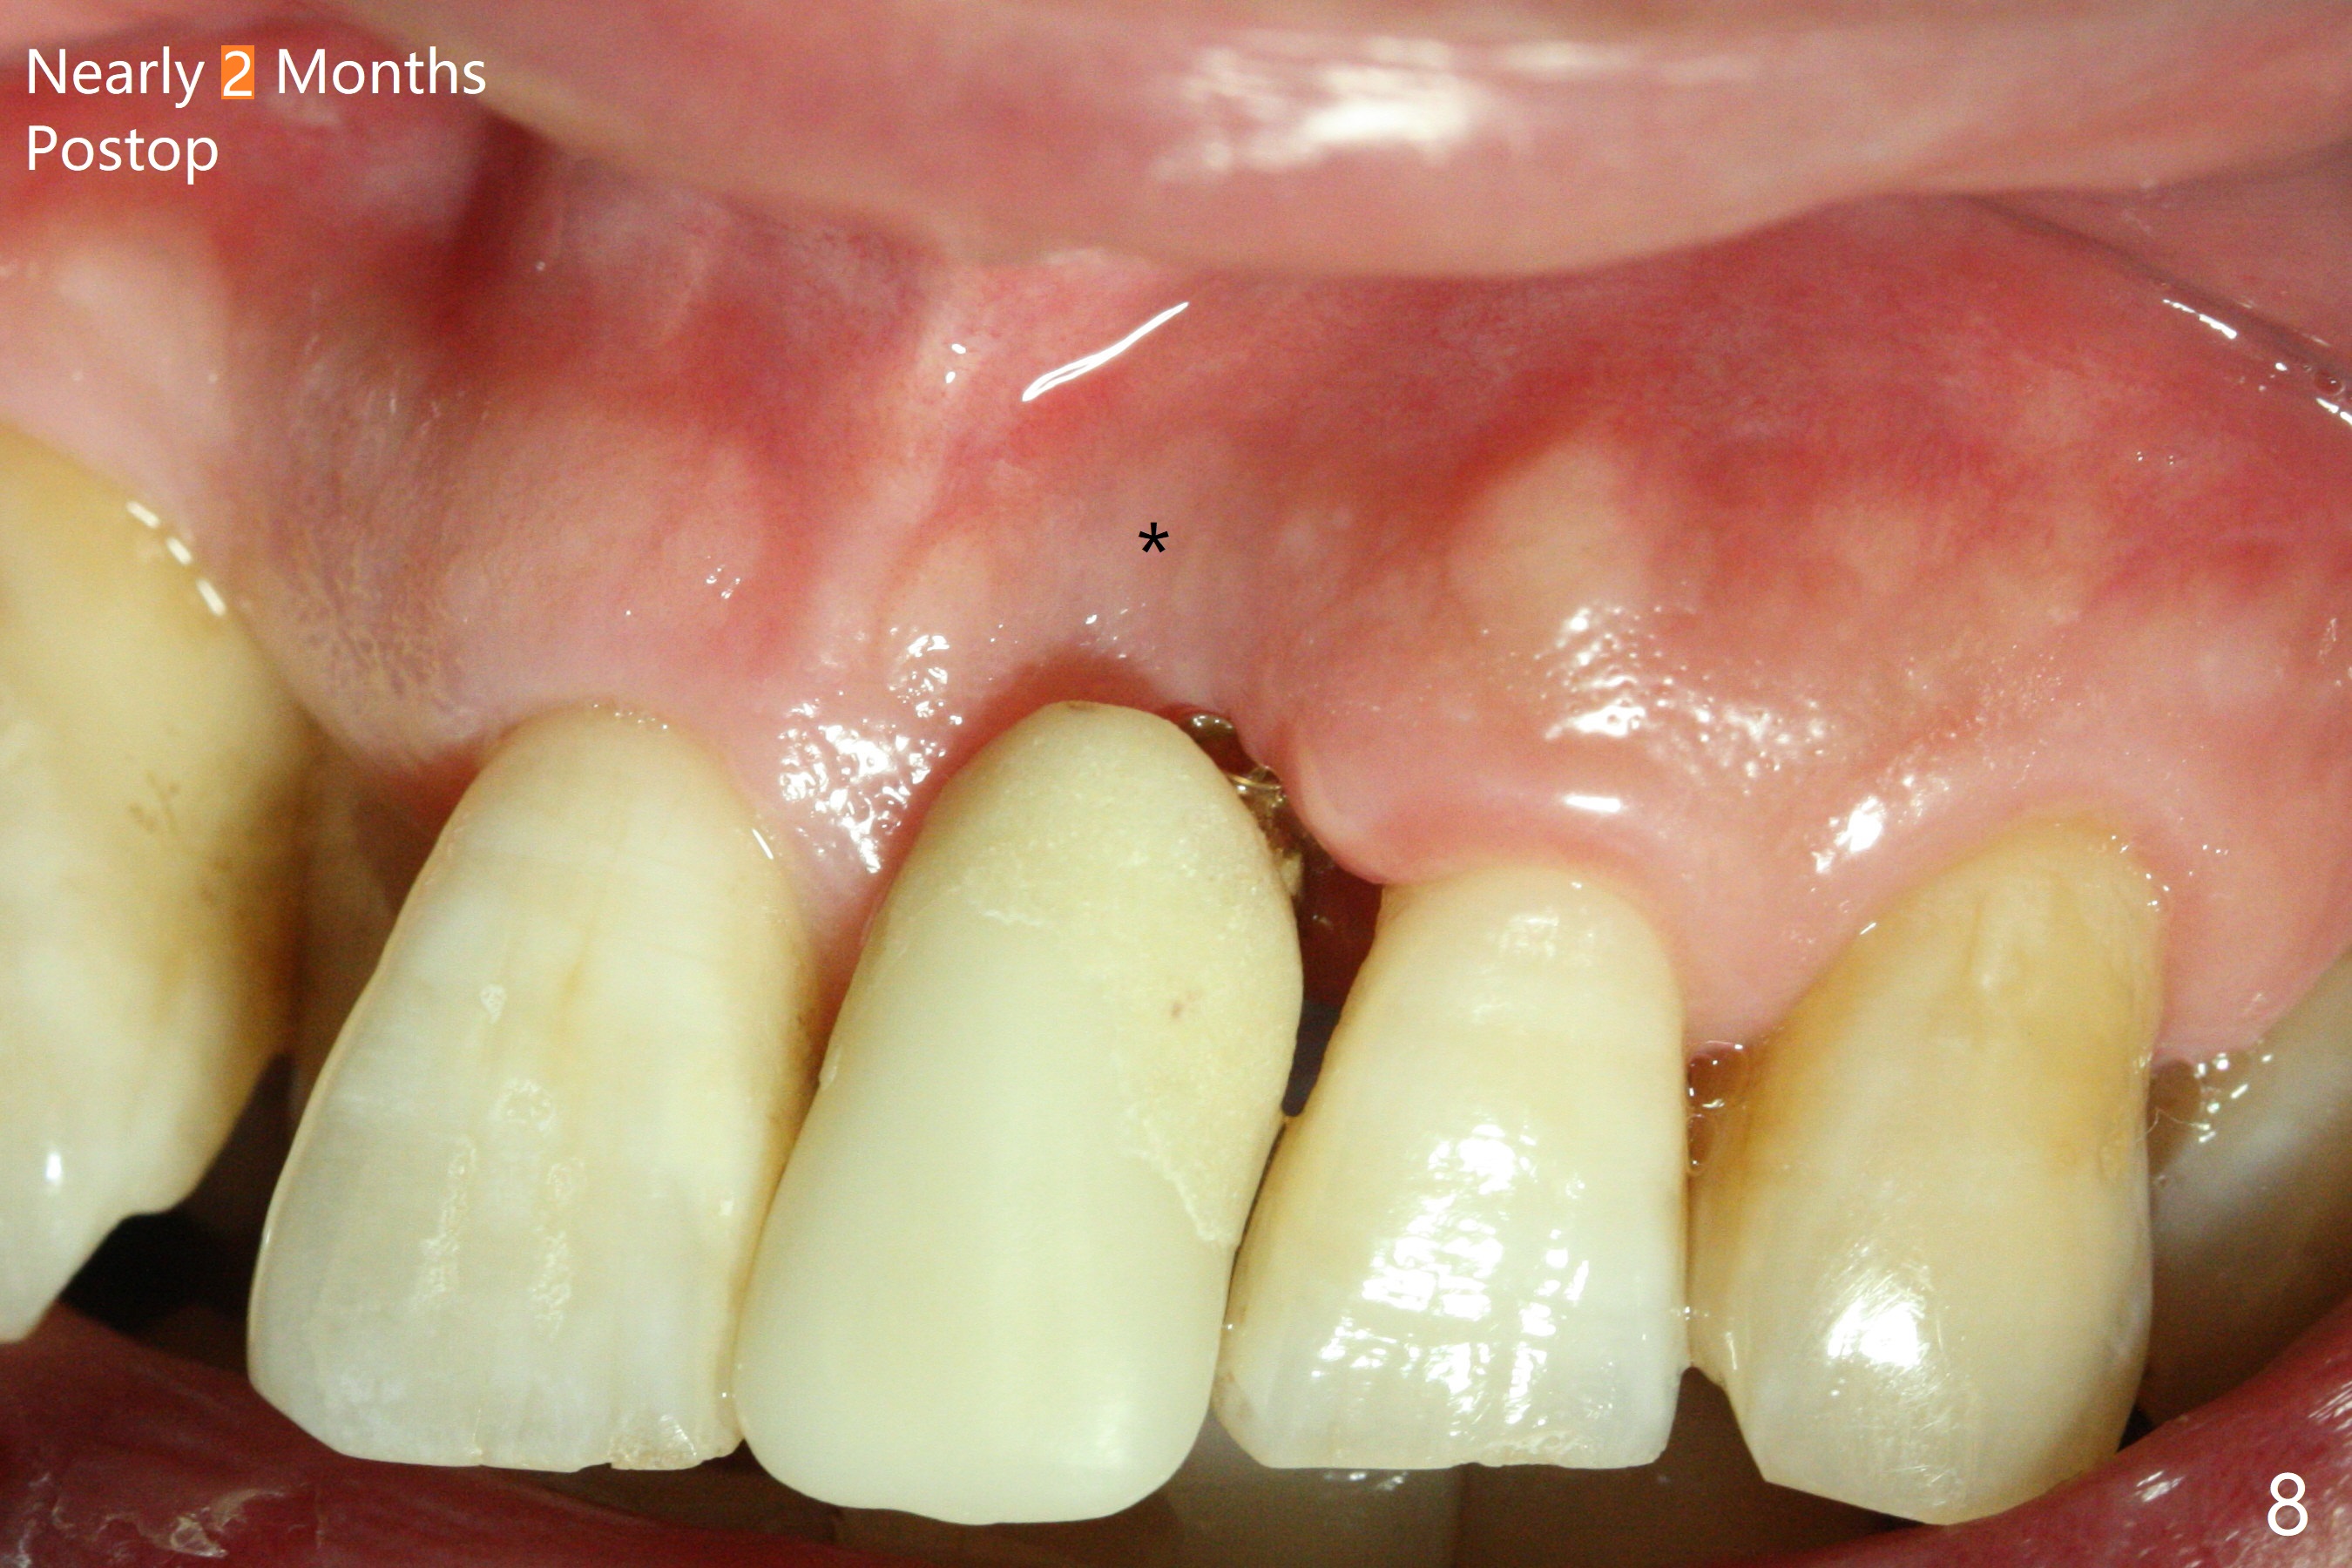

Immediately preop PA confirms loss of the buccal plate at #9 (Fig.1 *). In contrast the palatal crest is ~ 4 mm subgingival (WNL) after extraction. When initial osteotomy reaches 18 mm, there is moderate hemorrhage, probably due to close to the nasal floor (Fig.2 red dashed line). Following sequential osteotomy, a 3.8x15 mm dummy implant is placed partially (Fig.3 (pink: apical osteotomy)). After placement of an implant with the same dimension as the dummy's (Fig.4), PRF is laid against the inner surface of the buccal defect and allograft (Fig.5 *) is packed mainly in the buccal gap before and after insertion of a 4.5x5(4) mm abutment. The patient is satisfied with the immediate provisional (Fig.6: 1 week postop). The buccal margin of the provisional is shortened with exposure of bone graft to facilitate gingival downgrowth (Fig.6: 1 month postop). The buccal plate seems to collapse nearly 2 months postop (Fig.8 *), probably due to loss of the bone graft. The abutment is exposed buccally (Fig.9). The margin of the abutment is reprep and the provisional is relined so that the margin of the provisional is palatal to the buccal gingival margin. In 2-3 weeks, a temporary abutment will be used to bulk the buccal gingiva. The gingiva seems to have downgrown; the buccal plate collapse appears normal nearly 3 months postop (Fig.10). The patient is more concerned about cross bite at #7. A temporary abutment is not used. The bone graft remains in place 3.5 and 4.5 months postop (Fig.11,12 *). Between 3 and 4 months postop, the mesial surface of the abutment has been trimmed (Fig.12 >). Since the mesial surface of the tooth #10 will be reduced (white curved line) to correct the upper dental midline, an angled abutment (red line) seems to be necessary to shift the provisional distal.